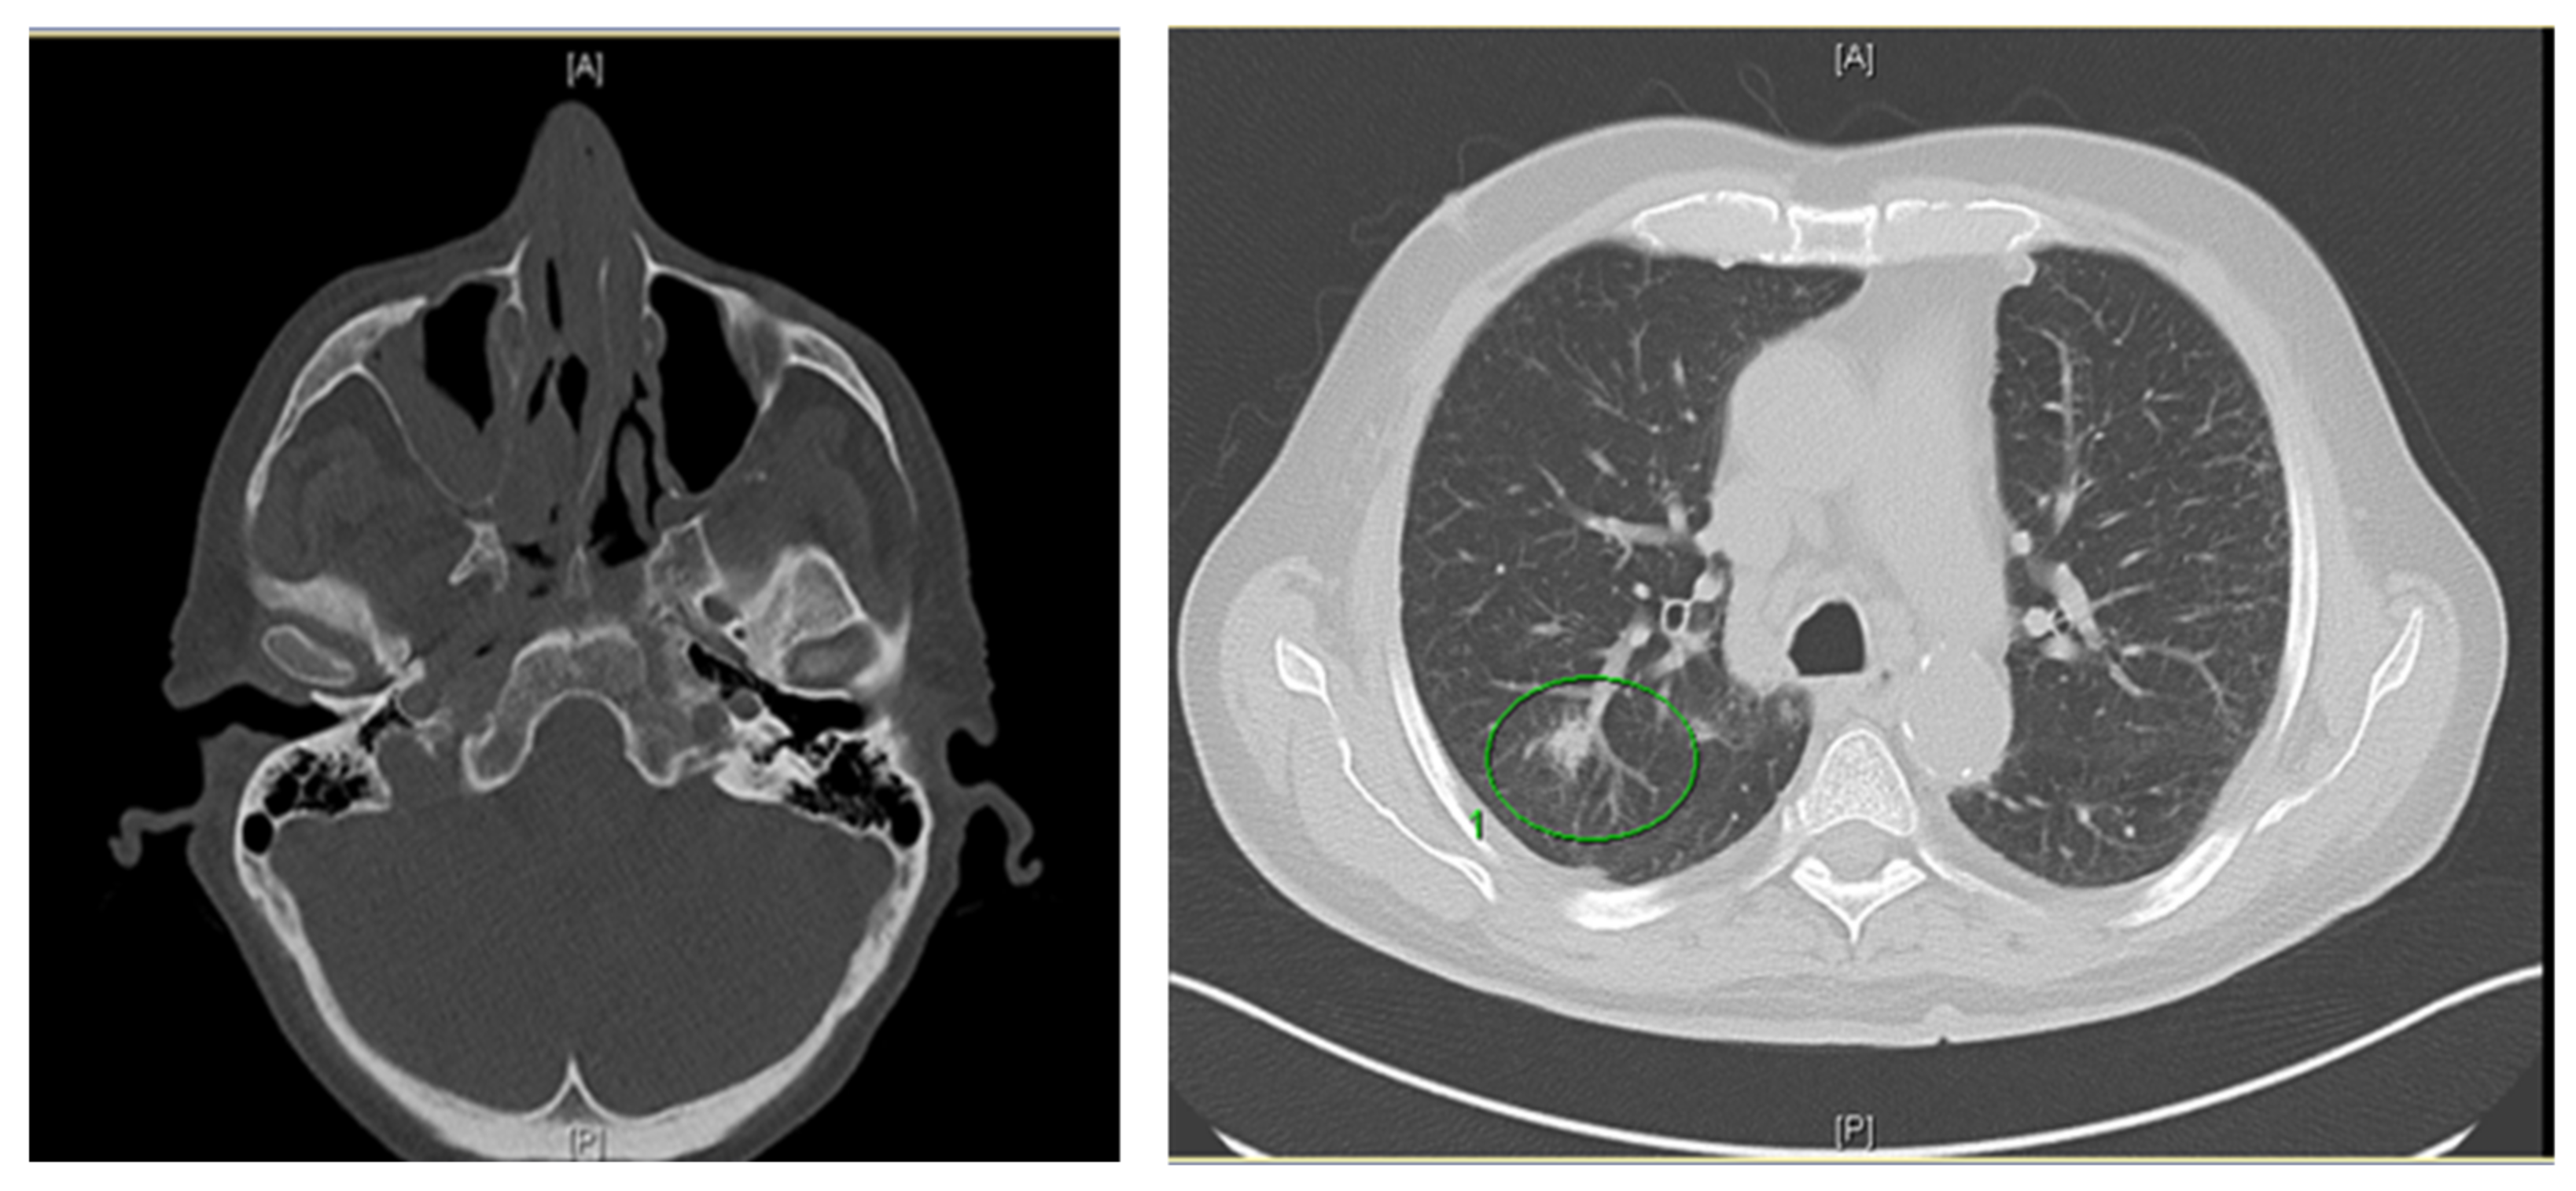

2. Case Report